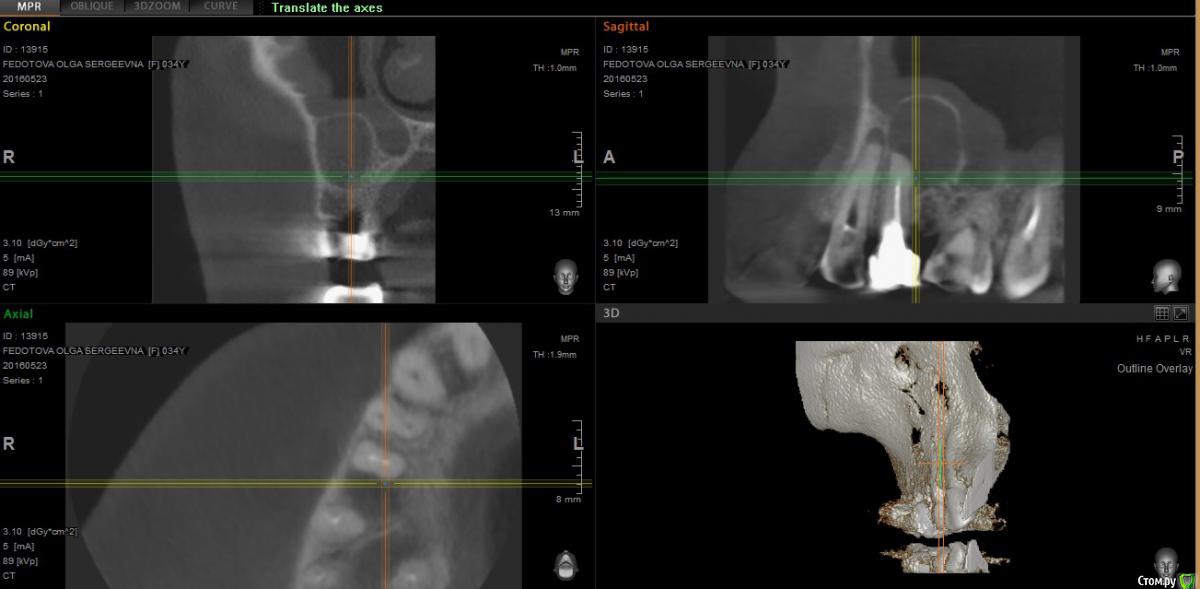

paciente Опубликовано 16 ноября, 2015 Автор Поделиться Опубликовано 16 ноября, 2015 Здравствуйте! Решила поднять тему. Хирург рекомендовал переделать КТ, т. к. предыдущее было плохого качества. По новому КТ перфорации в пазуху нет. Рекомендуют удалить пятый зуб и вычистить кисту. Но разошлись мнения врачей по поводу четвертого и шестого зубов: перелечить их перед удалением пятого зуба и кисты (но есть большой риск воспаления) или оставить как есть и наблюдать.Записалась на удаление на пятницу, но есть сомнения: лечить-не лечить?Если не сложно, посмотрите, пожалуйста новое КТ. Здесь, на форуме, рекомендовали лечить, но возможно, новые данные КТ как-то меняют ситуацию? Огромное спасибо за ответы и прошу прощения за настырность) https://yadi.sk/d/kDztiIEIkVfAh Ссылка на комментарий

paciente Опубликовано 11 июня, 2016 Автор Поделиться Опубликовано 11 июня, 2016 Здравствуйте! Снова поднимаю тему.Начала перелечивание зубов под операцию. При перелечивании шестого зуба нашли обломок инструмента в канале, отправили к терапевту-микроскописту, вместе с ней решили попробовать консервативное лечение, до этого терапевты советовали только операцию.На данный момент перелечен четвертый зуб, пятый пока остался как есть, в шестом зубе перелечены три канала из четырех, все под временными пломбами.План доктора такой: 17-го июня постоянная пломбировка четвертого зуба, затем окончательное перелечивание шестого зуба и его постоянная пломбировка, как я поняла, одновременно, потом занимаемся пятым зубом. Смущает то, что хирурги говорили, что постоянная пломбировка делается в день операции, либо максимум за день. Подскажите, пожалуйста, правильна ли тактика врача в моем случае? Врач на мой вопрос ответила, что хирург не знает об имунном ответе и, если после временной пломбировки ничего не случилось, то и от постоянной тоже ничего не будет. Так ли это?Прикрепляю сканы свежего кт, оно сделано до перелечивания четвертого зуба под микроскопом.Спасибо большое за ответы! Ссылка на комментарий

paciente Опубликовано 11 июня, 2016 Автор Поделиться Опубликовано 11 июня, 2016 https://yadi.sk/d/vsNfYLs3sRjY9 Ссылка на комментарий